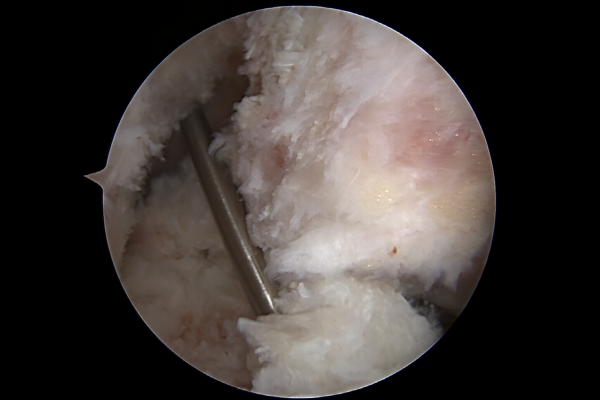

내시경 사진을 보시면 전방십자인대가 파열되어 보이지 않고, 잔해만 보이며, 인대가 파열되어 공간이 비어있는 드라이브-스루 사인(drive-through sign knee)이 확인됩니다.